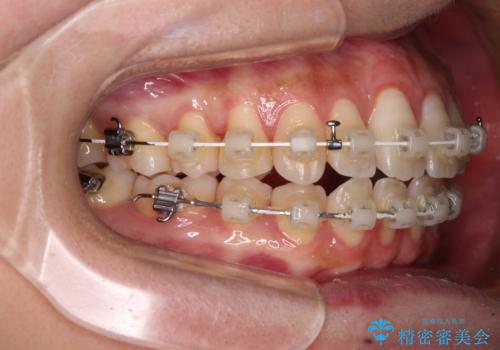

- 審美装置

当初は上記計画でしたが、レントゲン撮影よりインプラント埋入は困難と判断され、患者様と相談の上、歯を削ってブリッジとするよりも、奥歯の咬み合わせを多少妥協することとなっても、スペースを閉じて仕上げていくこととしました。

1年弱で治療方針を変更したため、治療期間は長くなりましたが、スペースは無事に閉じ、咬合の違和感なく仕上げることができました。